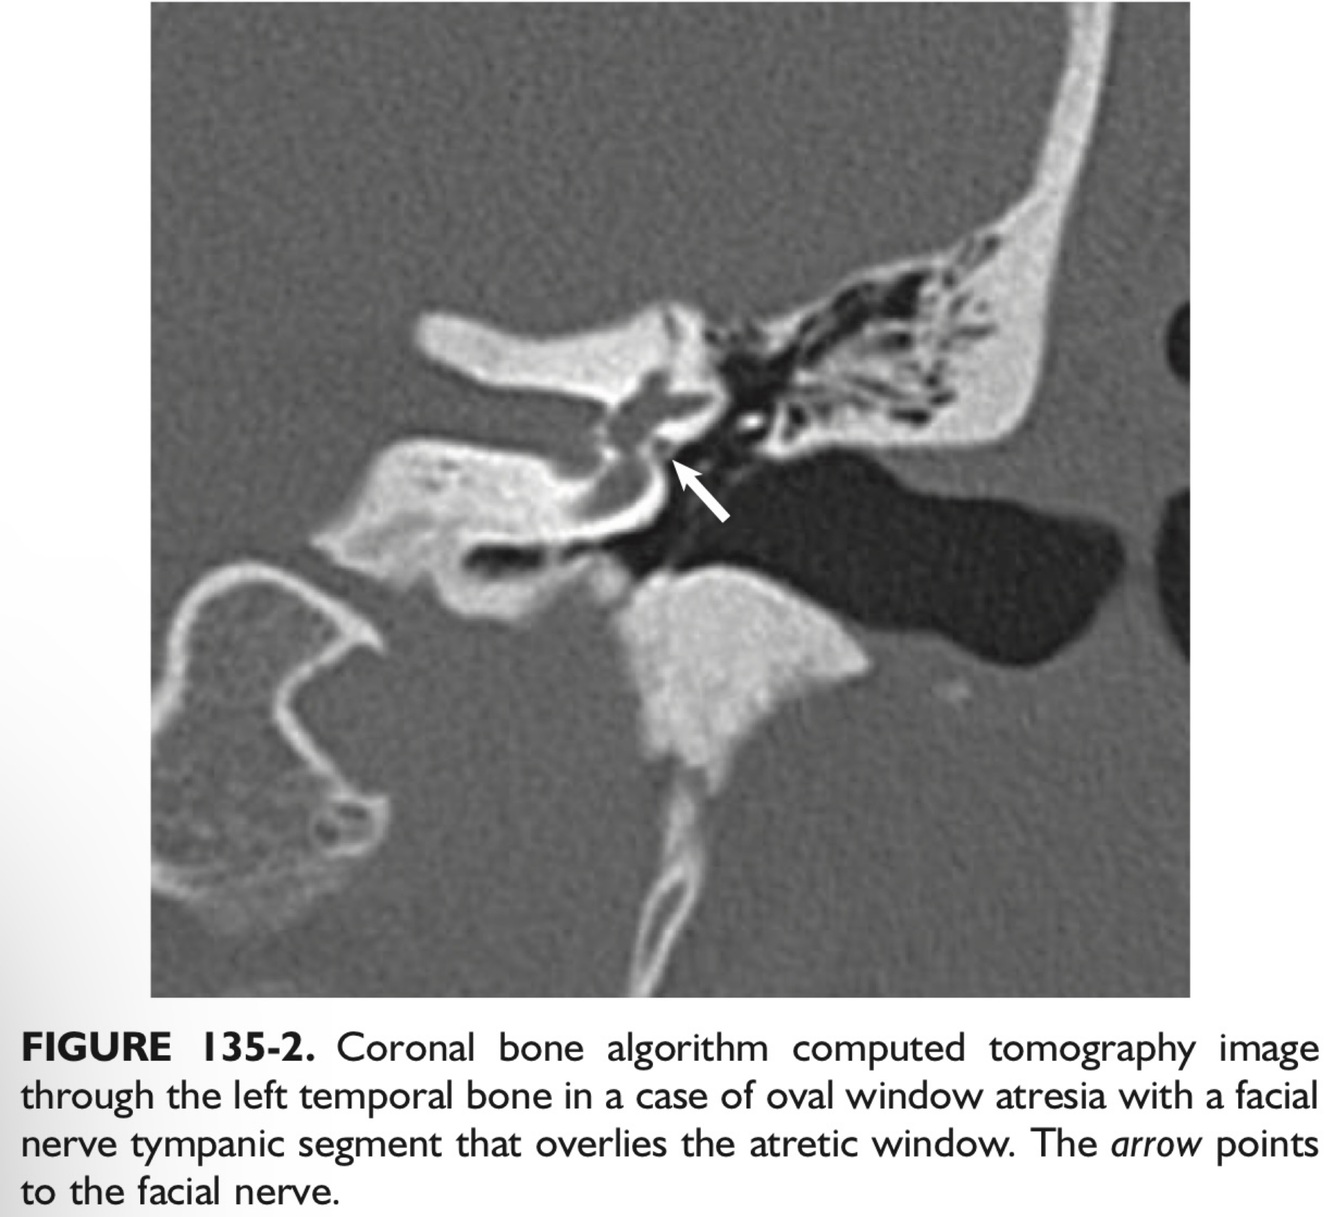

In a patient with atresia of the EAC, the FN tends to be dehiscent in the ___ segment and can overlie the ___.

In a patient with atresia of the EAC, the FN tends to be dehiscent in the tympanic segment and can overlie the oval window.